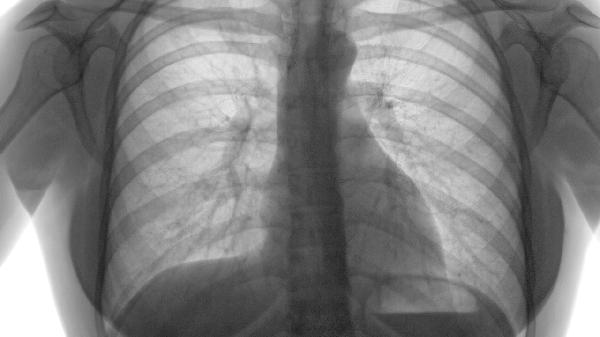

确诊需结合肺功能检查显示残气量增加、弥散功能下降,胸部CT可见肺野透亮度增高伴肺大疱形成。这些客观指标均指向器质性病变,与结核分枝杆菌培养阳性或病毒核酸检测等传染性疾病诊断标准有本质区别。